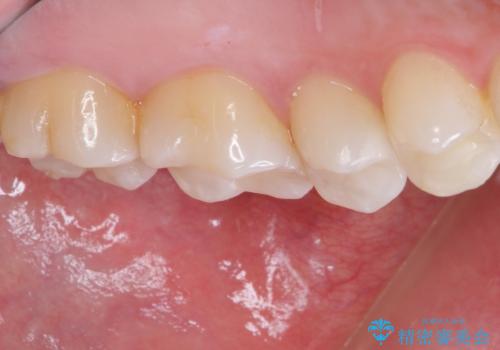

そして次の来院時、セラミックインレーを装着し、噛み合わせなどの調整を行います。

自然な色調で大変満足されました。